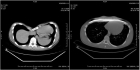

Владимир Кузьмичев: Аномалии грудной клетки — это пороки развития, если речь идет о врожденных деформациях, и результат различных заболеваний (главным образом травм), если мы говорим о приобретенных случаях. В медицинской среде известны несколько типов деформации: воронкообразная грудная клетка, килевидная деформация грудной клетки и другие, более редкие типы деформации — Синдром Поланда, врожденная расщелина грудины, и т.д. Проявлением воронкообразной груди или «груди сапожника», как ее еще называют, является западение грудины и ребер, в результате чего образуется углубление различной степени выраженности. Килевидная деформация («куриная грудь») представляет собой выступание передней поверхности грудины. Степень проявления каждого из типов деформации может быть различной.

Владимир Кузьмичев: Сегодня устранить структурную компрессию грудной клетки можно при помощи различных методик, общее число которых превышает 50. При лечении воронкообразной деформации мы предпочитаем метод Насса, так называемый миниинвазивный метод коррекции. Во время операции хирург делает 2 разреза по передней подмышечной линии, устанавливает за грудину титановую пластину и фиксирует ее в нужном положении. Пластина оказывает давление и выпрямляет грудину. Уже на операционном столе грудная клетка принимает правильную форму. D типичной ситуации продолжительность операции около одного часа. Пациент встает уже на следующий день, а выписывается из стационара через 6-7 дней.